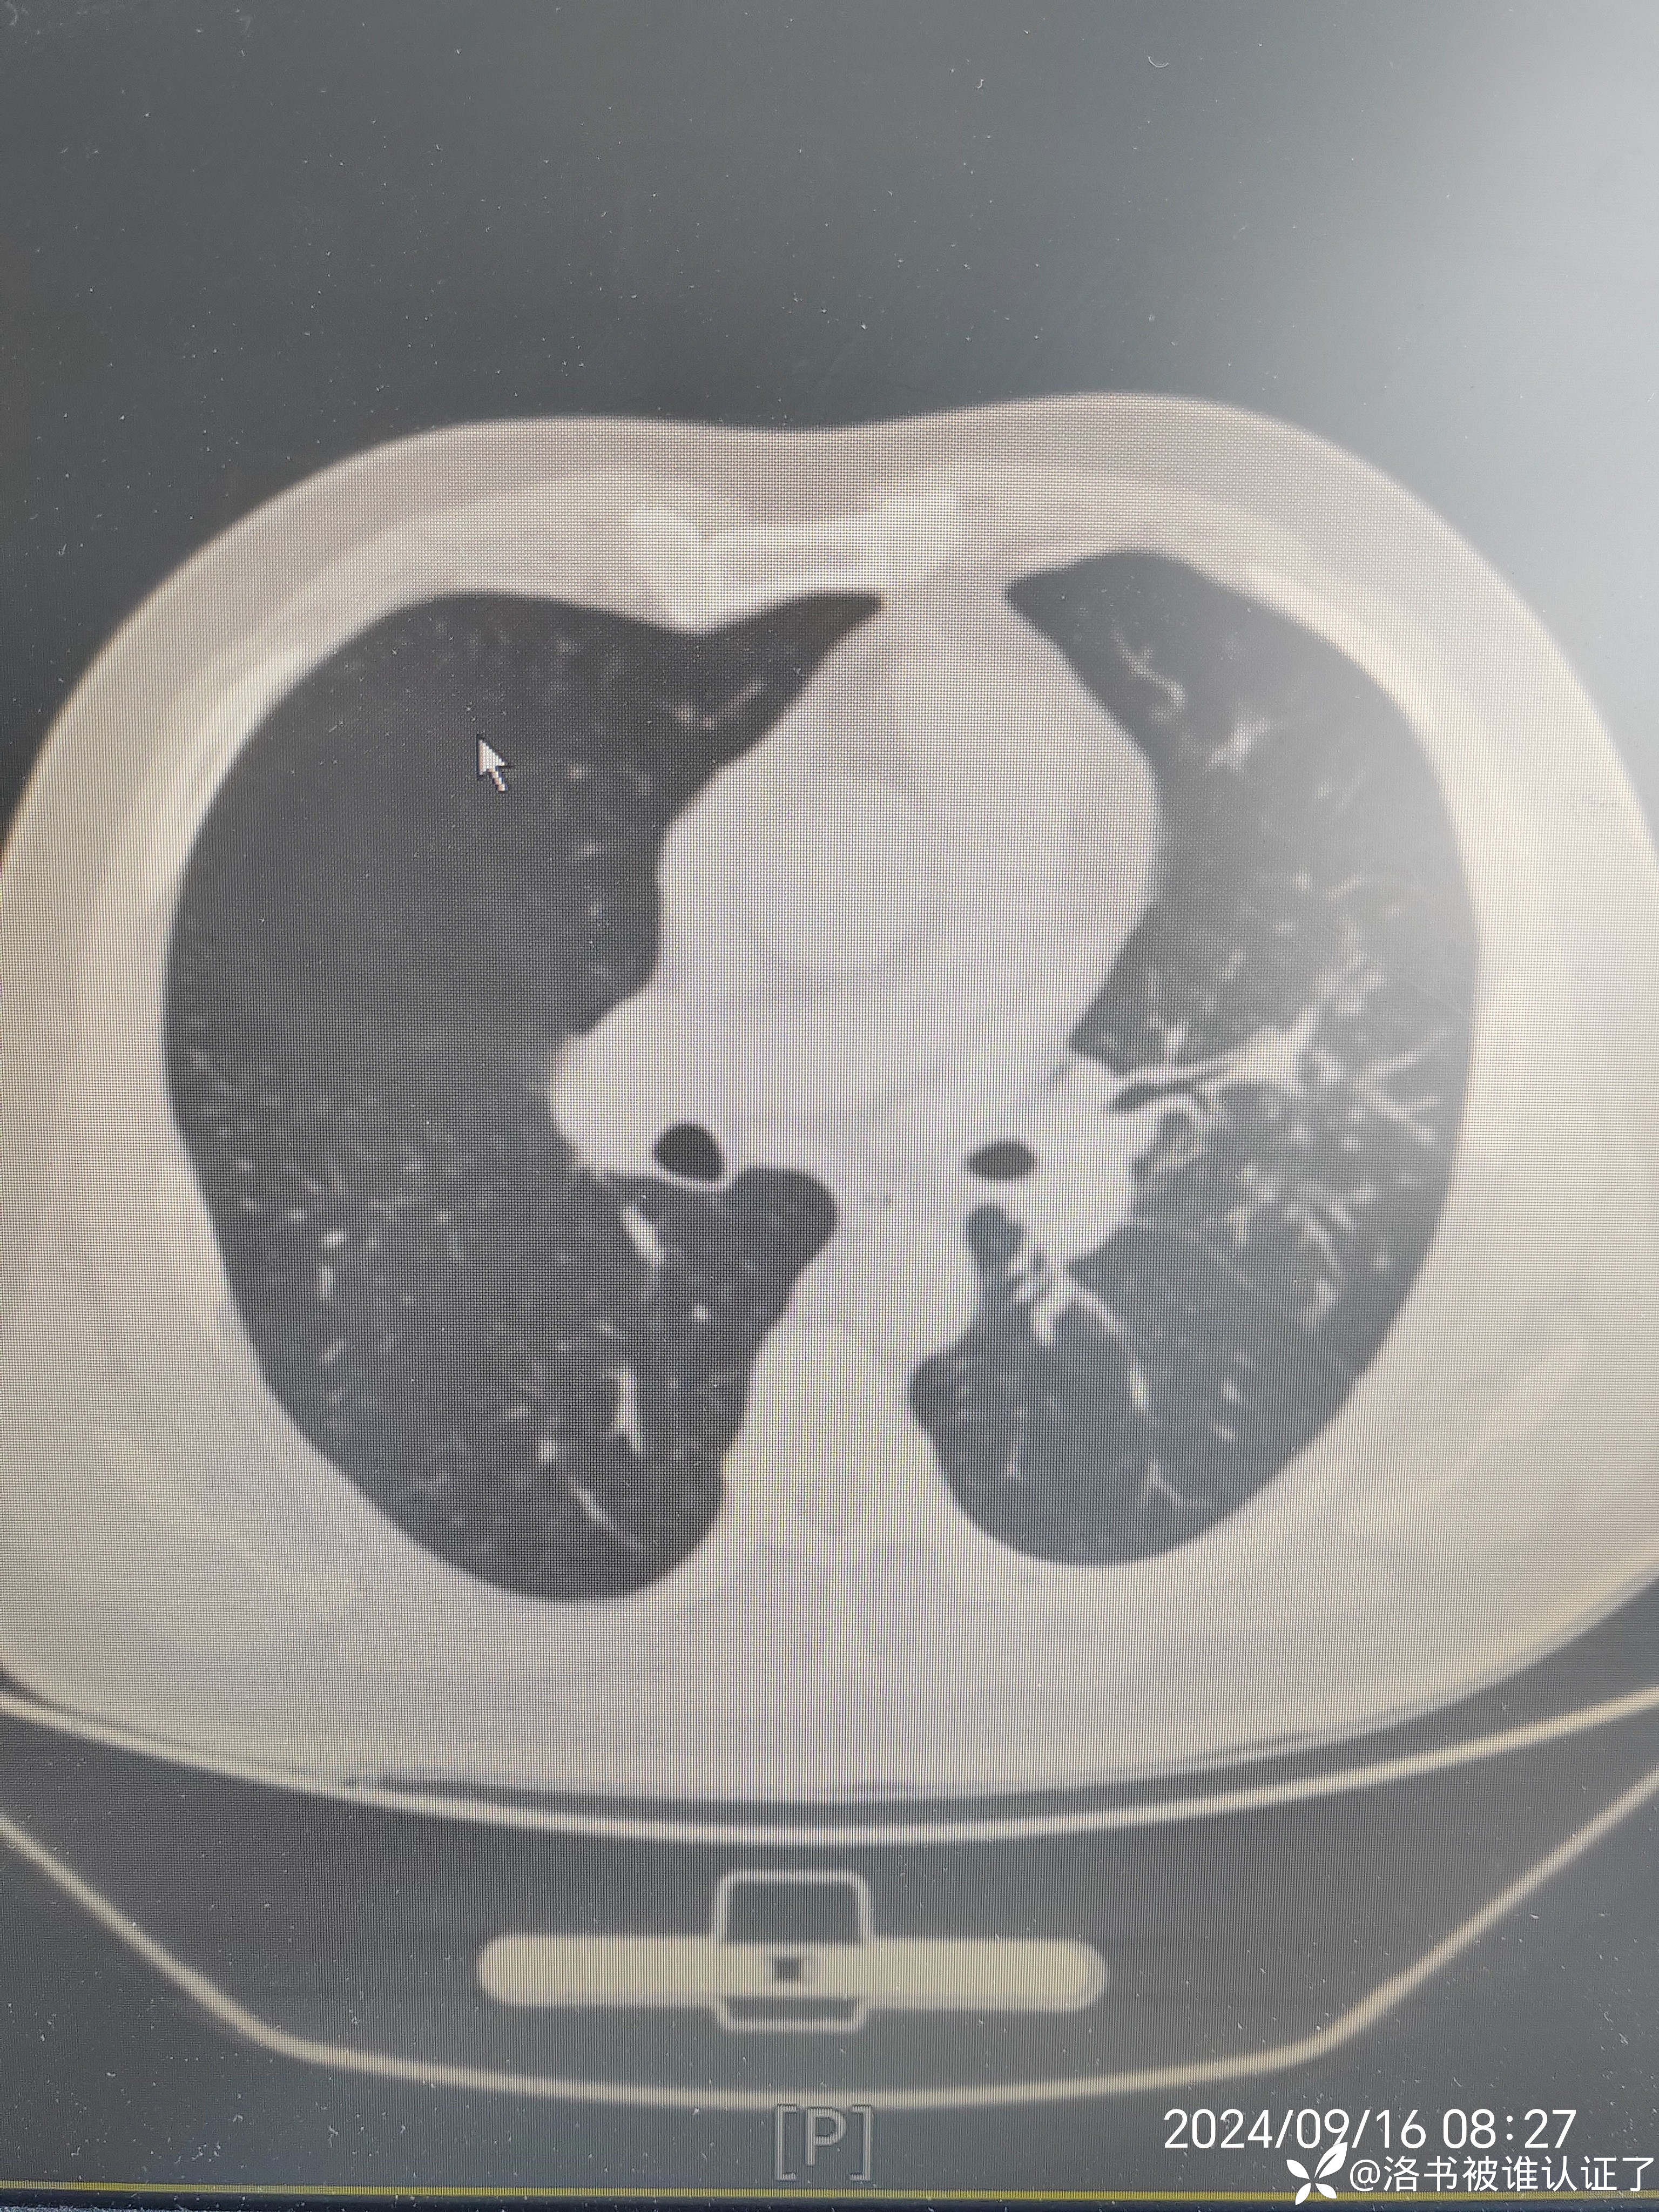

【检查】胸部CT示肺炎。

【临床诊断】:肺炎